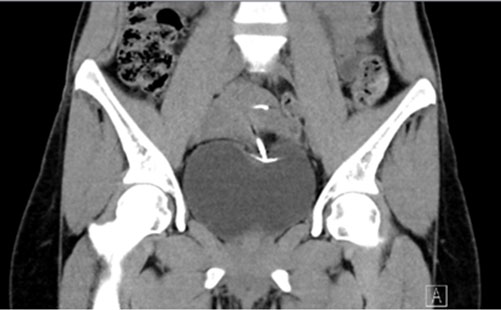

A migration diagnosis can be reached through ultrasound and plain film [7]. In our case, the diagnosis was confirmed through a cystoscopy performed by an outpatient urologist. To investigate further, we decided to perform a CT scan to ensure the extension and location of the IUD (Figure 2 and Figure 3).

Figure 2: A coronal section of the patient’s abdominal CT scan reveals the dislocated IUD in the bladder and the uterus.